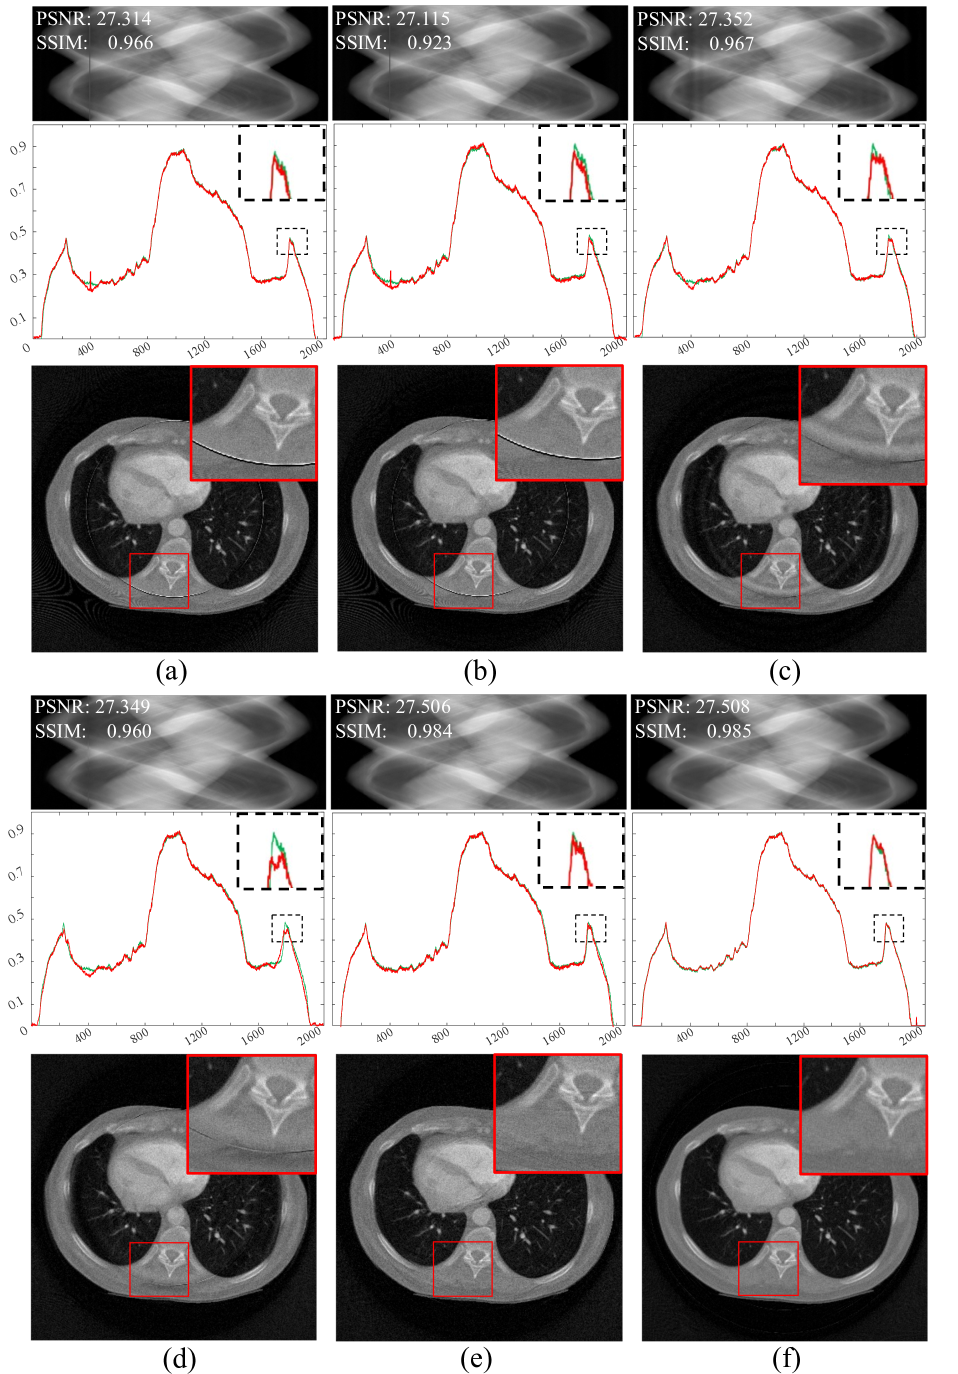

Refer to caption

Figure 7: Comparison experiments with simulated data. (a) Normalization method. (b) Regularization method. (c) W-FFT method. (d) FFT method. (e) Combination method. (f) Proposed method. The display range is [0, 1] for the sinogram and [0, 0.0015] for the CT images.

The experimental results are shown in Fig. 7, which presents the corrected sinograms and provides a quantitative comparison with the reference sinogram regarding PSNR and SSIM. Higher scores indicate better consistency with the reference sinogram. The second row displays the profile curves of the 200th row, with the green curve representing the reference profile and the red curve showing the predicted profile. The third row shows the reconstructed images and their local zoom-in views.

Zoom-in views (a) to (d) in Fig. 7 reveal some ring artifacts, indicating limitations in suppressing defective pixels with these methods. In contrast, the zoom-in views in Fig. 7 (e) and Fig. 7 (f) show reduced ring artifacts, with Fig. 7 (f) exhibiting the least. The image in Fig. 7 (e) presents other types of artifacts. In the profile curves of the 200th row, Fig. 7 (a) to Fig. 7 (d) show noticeable deviations from the reference profile curve in columns 400 to 404. The quantitative evaluation results indicate that the PSNR value of the predicted IS in Fig. 7 (f) performs best among all compared methods, suggesting an advantage in signal fidelity and the suppression of stripe artifacts. Quantitative evaluation results indicate that the SSIM value of Fig. 7 (f) is the highest among all the compared images, demonstrating that this method offers significant advantages in signal fidelity and noise suppression.

In summary, the proposed method performs well in suppressing stripe artifacts and accurately estimating the IS values of defective pixels, thereby improving the quality of image reconstruction to a certain extent.

To verify the effectiveness of the two unidirectional gradient constraints and their role in removing ring artifacts from CT images through the sorted sinogram, we used the simulated sinogram shown in Fig. 6 (b). Fig. 11 presents the results obtained by applying different unidirectional gradient constraints to INR, with the number of training iterations fixed at 10,000. The first rows of Fig. 11 show the INR-parameterized IS, respectively, with PSNR and SSIM scores annotated in the figures. The second rows display the profile lines of the 200th row. The green lines represent the reference profile, while the red lines represent the profile lines of the INR-parameterized IS.

Figure 11: Impact of unidirectional gradient constraints on INR-parameterized IS: (a) Angular gradient with L1subscript𝐿1L_{1}italic_L start_POSTSUBSCRIPT 1 end_POSTSUBSCRIPT constraint applied to SA only; (b) Detector gradient with L2subscript𝐿2L_{2}italic_L start_POSTSUBSCRIPT 2 end_POSTSUBSCRIPT constraint applied to IS only; (c) Combined angular gradient with L1subscript𝐿1L_{1}italic_L start_POSTSUBSCRIPT 1 end_POSTSUBSCRIPT constraint on SA and detector gradient with L2subscript𝐿2L_{2}italic_L start_POSTSUBSCRIPT 2 end_POSTSUBSCRIPT constraint on IS; (d) Combined angular gradient with L1subscript𝐿1L_{1}italic_L start_POSTSUBSCRIPT 1 end_POSTSUBSCRIPT constraint on SA and weighted detector gradient with L2subscript𝐿2L_{2}italic_L start_POSTSUBSCRIPT 2 end_POSTSUBSCRIPT constraint on IS; (e) Unsorted IS and SA with combined angular gradient and L1subscript𝐿1L_{1}italic_L start_POSTSUBSCRIPT 1 end_POSTSUBSCRIPT constraint on SA and detector gradient with L2subscript𝐿2L_{2}italic_L start_POSTSUBSCRIPT 2 end_POSTSUBSCRIPT constraint on IS. The disparity range is set to [0, 1].

From the observations in Fig. 11 (a) and Fig. 11 (b), it is clear that the IS shown in Fig. 11 (a) exhibits significant stripe artifacts. However, the IS of Fig. 11 (b) shows less prominent stripe artifacts, although the profile plot reveals that the IS profile is overly smooth. This indicates that applying only the angular direction gradient L1subscript𝐿1L_{1}italic_L start_POSTSUBSCRIPT 1 end_POSTSUBSCRIPT constraint on the SA is insufficient for effectively removing stripe artifacts. Adding a gradient L2subscript𝐿2L_{2}italic_L start_POSTSUBSCRIPT 2 end_POSTSUBSCRIPT constraint in the detector direction on the IS can somewhat reduce stripe artifacts, but may also lead to overly smooth images. Further observation of Fig. 11 (c) and Fig. 11 (d) shows that all neural network parameterized IS effectively mitigate stripe artifacts. However, the quantitative metrics indicate that the PSNR and SSIM of Fig. 11 (d) are higher than those of Fig. 11 (c), demonstrating the effectiveness of the detector-direction gradient weighting strategy. In contrast, the profile lines of Fig. 11 (e) in columns 200 and 1800 do not effectively match the reference profile. In comparison, the IS profile of Fig. 11 (d) more closely aligns with the reference profile. This suggests that applying a weighted gradient L2subscript𝐿2L_{2}italic_L start_POSTSUBSCRIPT 2 end_POSTSUBSCRIPT constraint in the detector direction on the sorted IS and an angular gradient L1subscript𝐿1L_{1}italic_L start_POSTSUBSCRIPT 1 end_POSTSUBSCRIPT constraint on the sorted SA effectively removes stripe artifacts while maintaining image edge sharpness. Comparing Fig. 7 (f) and Fig. 11 (d) reveals that the use of the residual compensation strategy further enhances the PSNR.